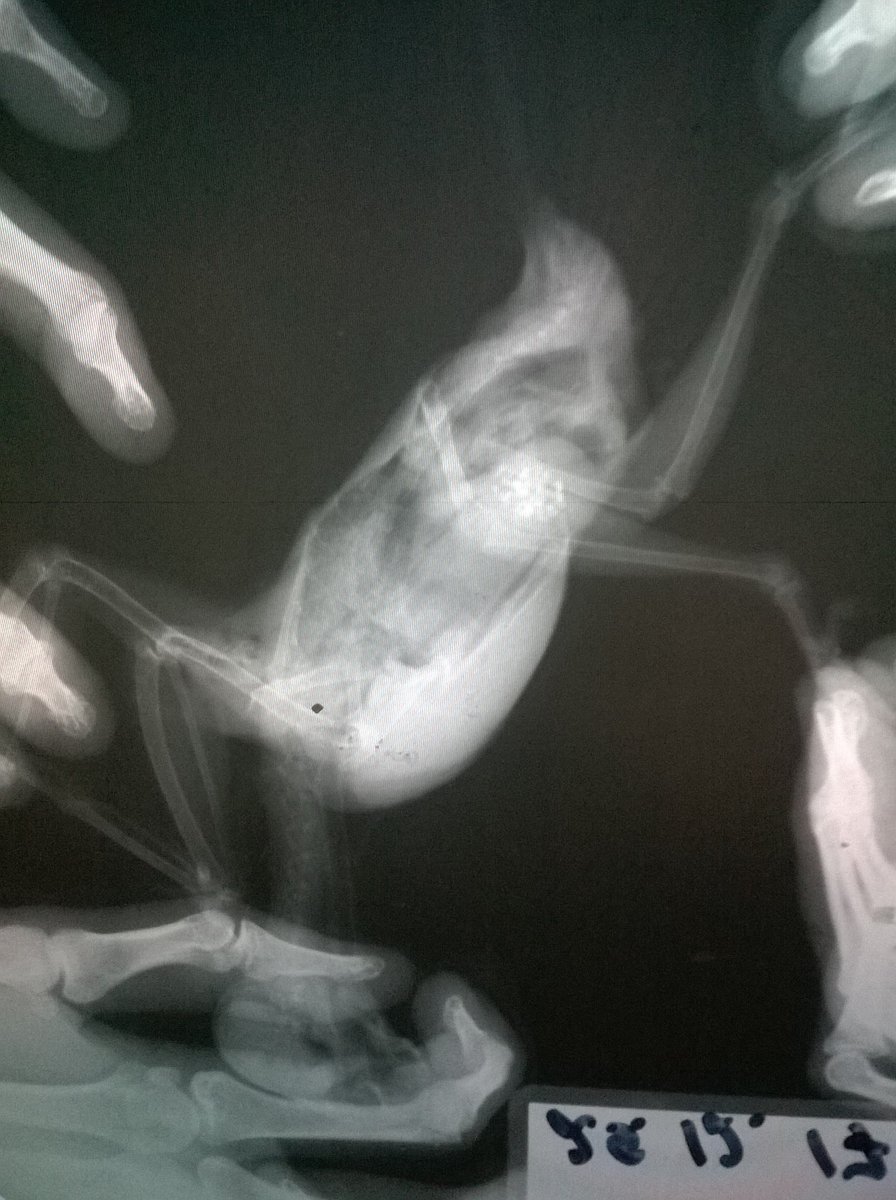

Возраст: 7 полных лет. Пол: женский. Порода: сизарь обыкновенный (Columba livia). Около 4-х месяцев назад голубка перестала нести яйца. Последние две пары снесенных яиц были значительно меньше обычных (не более 2 см.). Затем (в конце июля) появились странные выделения в помете (фото 1 и 2). Такие выделения начали выходить вместе с пометом примерно 1-2 раза в месяц. Когда у нее появляются эти странные выделения она ведет себя примерно так же, как во время кладки (хвост опущен, ищет место для кладки, разгребает, учащенно дышит). В остальное время голубка жизнерадостная и активная, ест и пьет хорошо, как обычно, летает, общается и т.д. Мы были у ветеринара, ей сделали рентген (фото 3 и 4). Доктор сказала, что у нее в брюшке эти сгустки - предположительно, остатки несформированного яйца. Эти сгустки могут накапливаться и давить на органы. Доктор предложила два способа решения: Инъекция (чего именно мы не знаем). При помощи этой инъекции, предположительно, голубка должна самостоятельно избавиться от этих сгустков, которые выйдут самостоятельно. Доктор сказала, что понаблюдает за ней в течение половины дня. Оперативное вмешательство. Если инъекция не подействует - доктор сказала что нужно будет делать операцию по очистке. Но при операции есть риск неудачного исхода. В общем от операции, над инъекцией думаем. Хотим собрать мнение еще нескольких специалистов, т.к. очень боимся возможного риска и не хотим сделать хуже. Пишу сюда, потому что хочу узнать мнения людей, встречавшихся с подобными ситуациями и так же мнения орнитологов и\или голубеводов, присутствующих на этом форуме. Заранее спасибо всем за ответ!- 3 ответа

Неразлучник перестал летать, когда посмотрела, обнаружила на внутренней стороне крыла шишечку, сделали рентген, фото прикладываю. Не летает, крыло отпустилось и дрожит, продолжается больше месяца, обратиться больше не к кому, у нас нет специалистов в городе. Помет у попугая не менялся, активность хорошая, кушает тоже хорошо -

г.Новодвинск. Специалистов нет. Проблема: плохо ходит, падает, не ест. Помет изменился. Предположение: застревания яйца Попугай корелла самка 6 лет. Клеточное содержание. Практически без выпуска из-за собаки,детей.Неслась практически ежегодно. Корм только РИО для средних попугаев, не ограничено. Съедала много.Пила воды много. Овощи, зелень, мин.подкормка,сепии и т.п. в рационе отсутствовали. На окне в клетке в комнате. Проблемы начались в начале недели, после того как снесла яйцо. Упала с жердочки, и практически перестала ходить. Обратились к девушке волонтеру по птицам. Единственному человеку который хоть как то попытался помочь и отправил сюда. Рекомендовано: Рентген(сделан), анализы( бак.посев,копрограмма) НЕ ДЕЛАЮТ в гор.вет.лаб. Обратиться к специалисту(поэтому тут). Улучшить условия кормления и содержания(делаем). Помогите спасти птицу,пожалуйста.Ошибки осознали..исправим,но очень нужна помощь. Назначено: вазелиновое масло 0,4мл в клоаку, 0,1мл в клюв 1 раз в сутки. . Водяная баня. Кормление насильно через шприц запаренной крупой с яблочным пюре детским. Глюконат кальция ампульный по 0,05мл 1 раз в сутки, клюв. Мильгамма 1/8 таблетки в клюв. Энтеросгель 0,1мл в разведении 1:1 с водой. Нужна помощь в лечении(